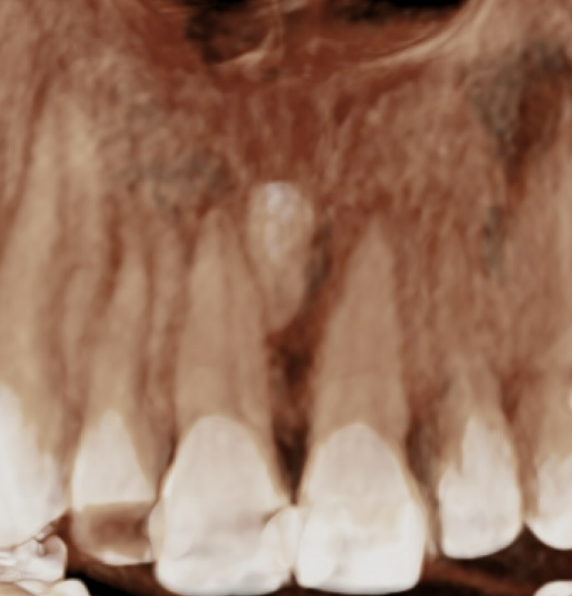

초진 정밀진단에서 확인되는 문제가 하나 더 있습니다.

앞니 사이의 과잉치입니다. 정가운데 위치한 과잉치를 정중과잉치 라고 합니다.

CT를 찍어 확인하니 과잉치의 위치가 신경관과 가깝고 깊어서 빼기가 쉽지 않습니다.

다행인점은 앞니의 이동을 최소화 하면 굳이 과잉치를 안 빼고도 교정치료가 가능한 상태라는 것입니다.